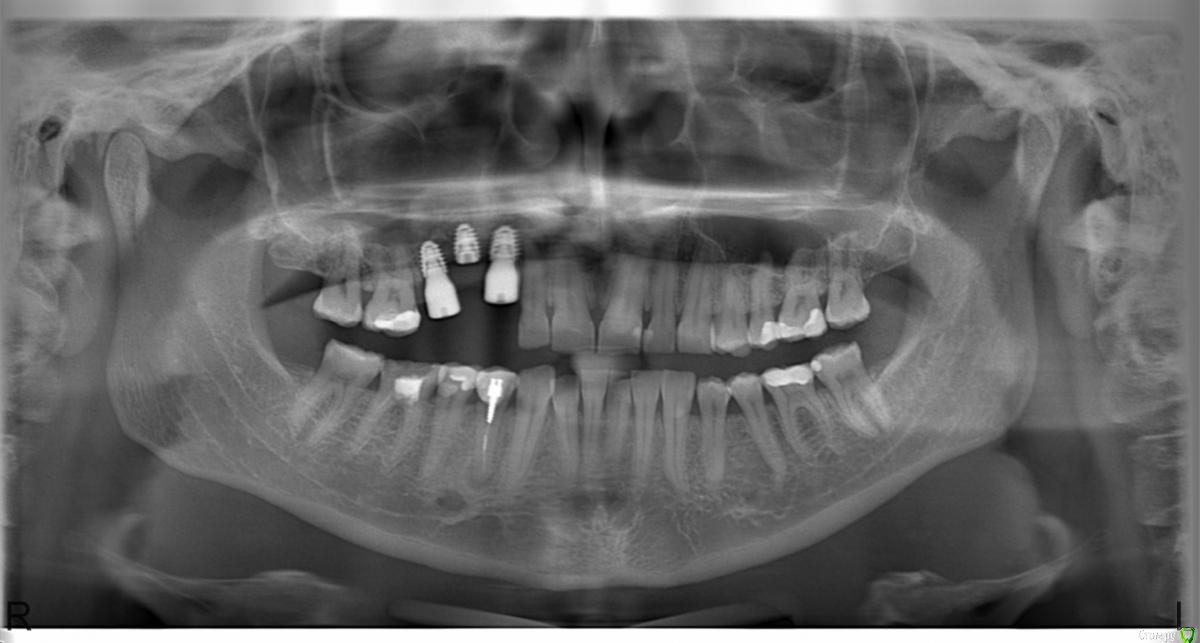

Lollipop Опубликовано 2 августа, 2015 Поделиться Опубликовано 2 августа, 2015 Уважаемые господа-хирурги!Большая просьба оценить результаты имплантации. По словам хирурга - все отлично, расстояние между коронками хорошее, с десневыми сосочками проблем быть не должно, по словам ортопеда - розовая керамика и отсутствие эстетики в связи с недостаточным горизонтальным расстоянием. В настоящий момент сосочки между формирователями абсолютно отсутствуют, десна имеет выгнутую кверху дугообразную форму. Кто прав - хирург или ортопед? Можно ли исправить ситуацию с десной подсадкой ССТ и какие перспективы у дальнейшего протезирования? Смущает так же близость верхушки имплантата и корня зуба 1.2.Заранее огромное спасибо!!!! Ссылка на комментарий

Aquarius Опубликовано 2 августа, 2015 Поделиться Опубликовано 2 августа, 2015 (изменено) Средний имплант, мягко говоря, здесь совсем не нужен) До корня двойки далеко, не волнуйтесь. Изменено 2 августа, 2015 пользователем Aquarius 2 Ссылка на комментарий

AlexanderGudkov Опубликовано 2 августа, 2015 Поделиться Опубликовано 2 августа, 2015 Перспективы протезирования - розовая керамика Ссылка на комментарий

Aquarius Опубликовано 2 августа, 2015 Поделиться Опубликовано 2 августа, 2015 Глушить имплант ( зашивать после выкручивания формирователя) и работать с мягкими тканями плюс временные коронки Ссылка на комментарий

Mane Опубликовано 2 августа, 2015 Поделиться Опубликовано 2 августа, 2015 Ситуация из простой перешла в очень сложную. Вам нужно заглушить или удалить средний имплантат. На оставшихся других провести пластику десны. Так как провал просто огромен, скорее всего 2 раза. Так же нужно восполнить убыль десны на зубе 1.2 (боковой резец). Иных вариантов нет. 2 Ссылка на комментарий